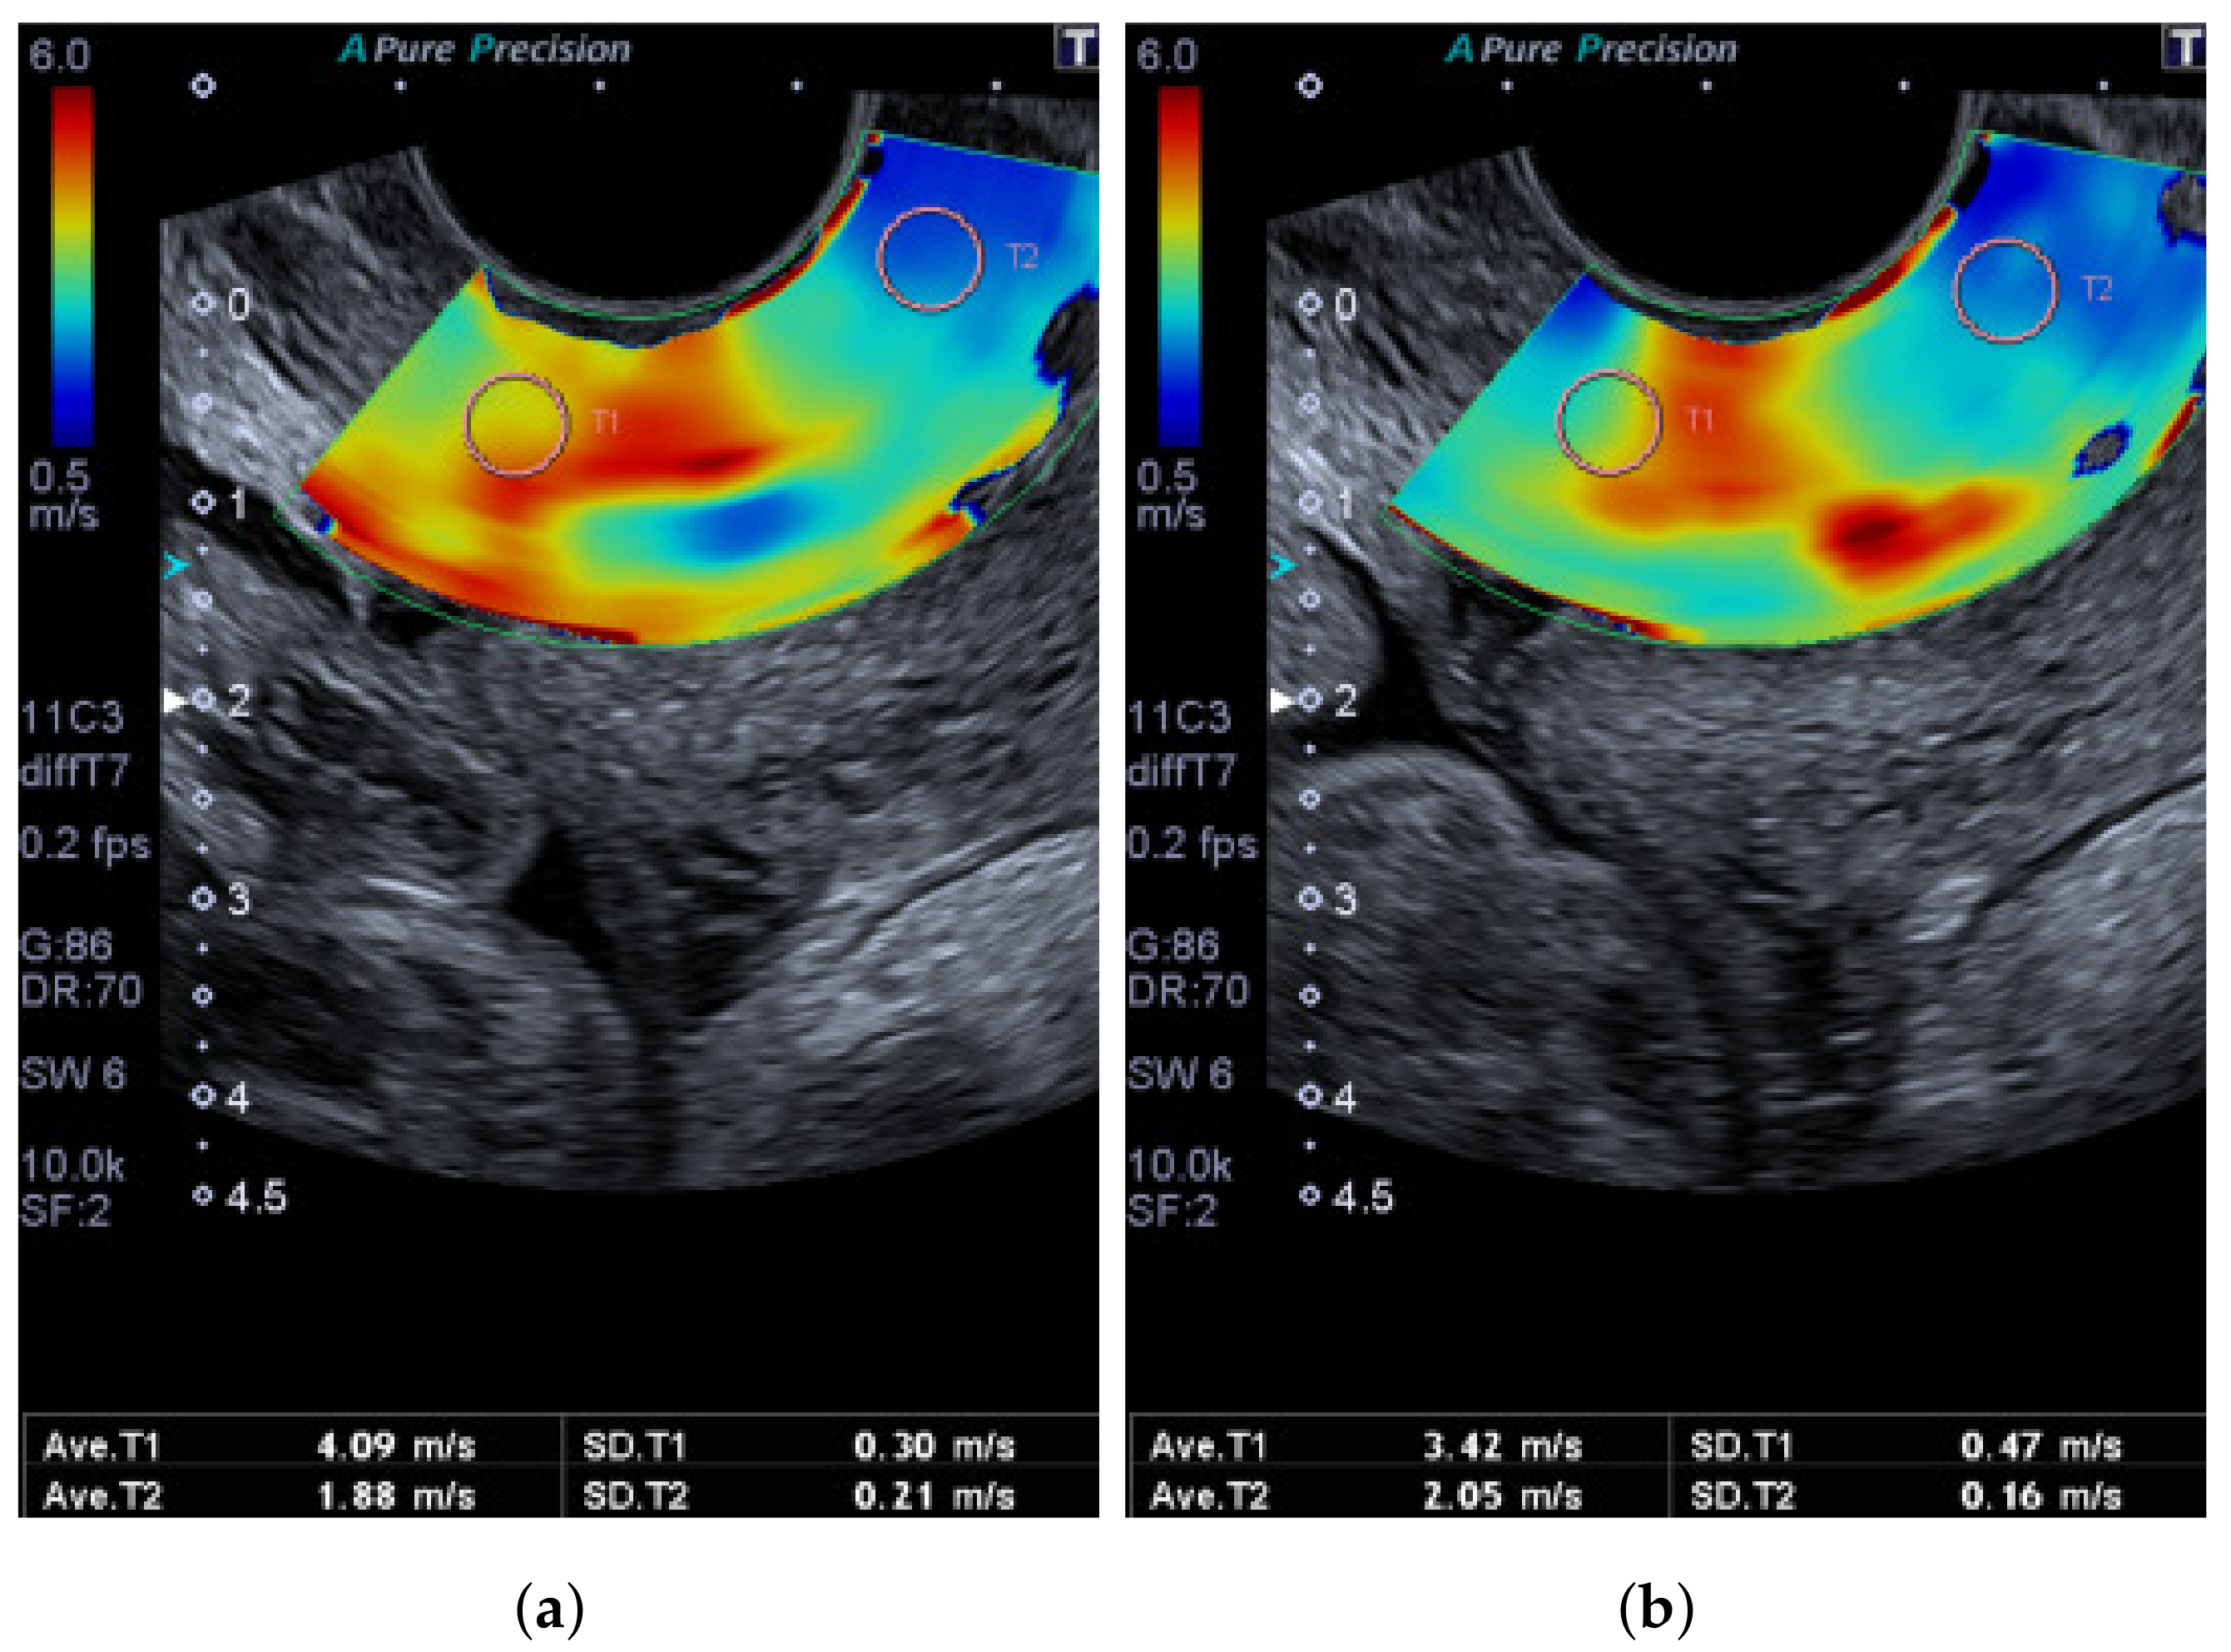

| Speed (No pressure) | 2.86 ± 0.75 | 2.30 ± 0.94 | 2.58 ± 0.69 |

| Speed (Pressure) | 3.63 ± 1.26 | 2.64 ± 0.94 | 3.14 ± 0.81 |